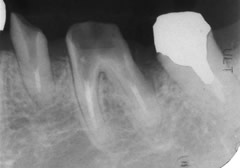

そしてこれが実際に心臓の病気になられた方の、口の中に残っていた重度の歯周病の歯です。

歯の根の先までが歯石(黒色)で覆われています。このような細菌のかたまりを口の中に残しておいて体にいいわけがありません。 歯周病が原因で脳疾患、心疾患、動脈硬化などになられた方の多くは、このような状態の歯でも抜かずに大切に残してきた傾向が強いと思われます。ある程度のところまで歯周病は進行してしまうと抜かざるをえなくなり、それが健康のためでもあるのです。

重度の歯周病の歯